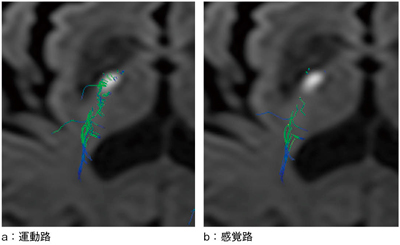

図6は,急性期脳梗塞が疑われてMRI検査を施行した症例である。その際,テンソル撮像を行い,DTI解析を施行した。本症例では,運動路と感覚路の2つの神経線維路の描出を試みた。運動路は皮質脊髄路を起点とし,中心前回を終点としたROIを設定した。感覚路は内側毛帯を起点とし,中心後回を終点としたROIを設定した。このDTI解析結果を,図7,8にそれぞれ示している。運動路にターゲットROIを設定した場合,図8 aに示すように運動路と感覚路の両神経線維が描出された。しかし,図8 bに示すように,感覚路にターゲットROIを設定した場合,脳梗塞部には運動路神経線維の存在は認められず,感覚路神経線維の存在が認められ,神経学的所見と一致していた。今後,ROIの設定場所や解析精度についてさらなる検討が必要となるであろう。

図7 DTI解析結果

図8 DTI解析結果